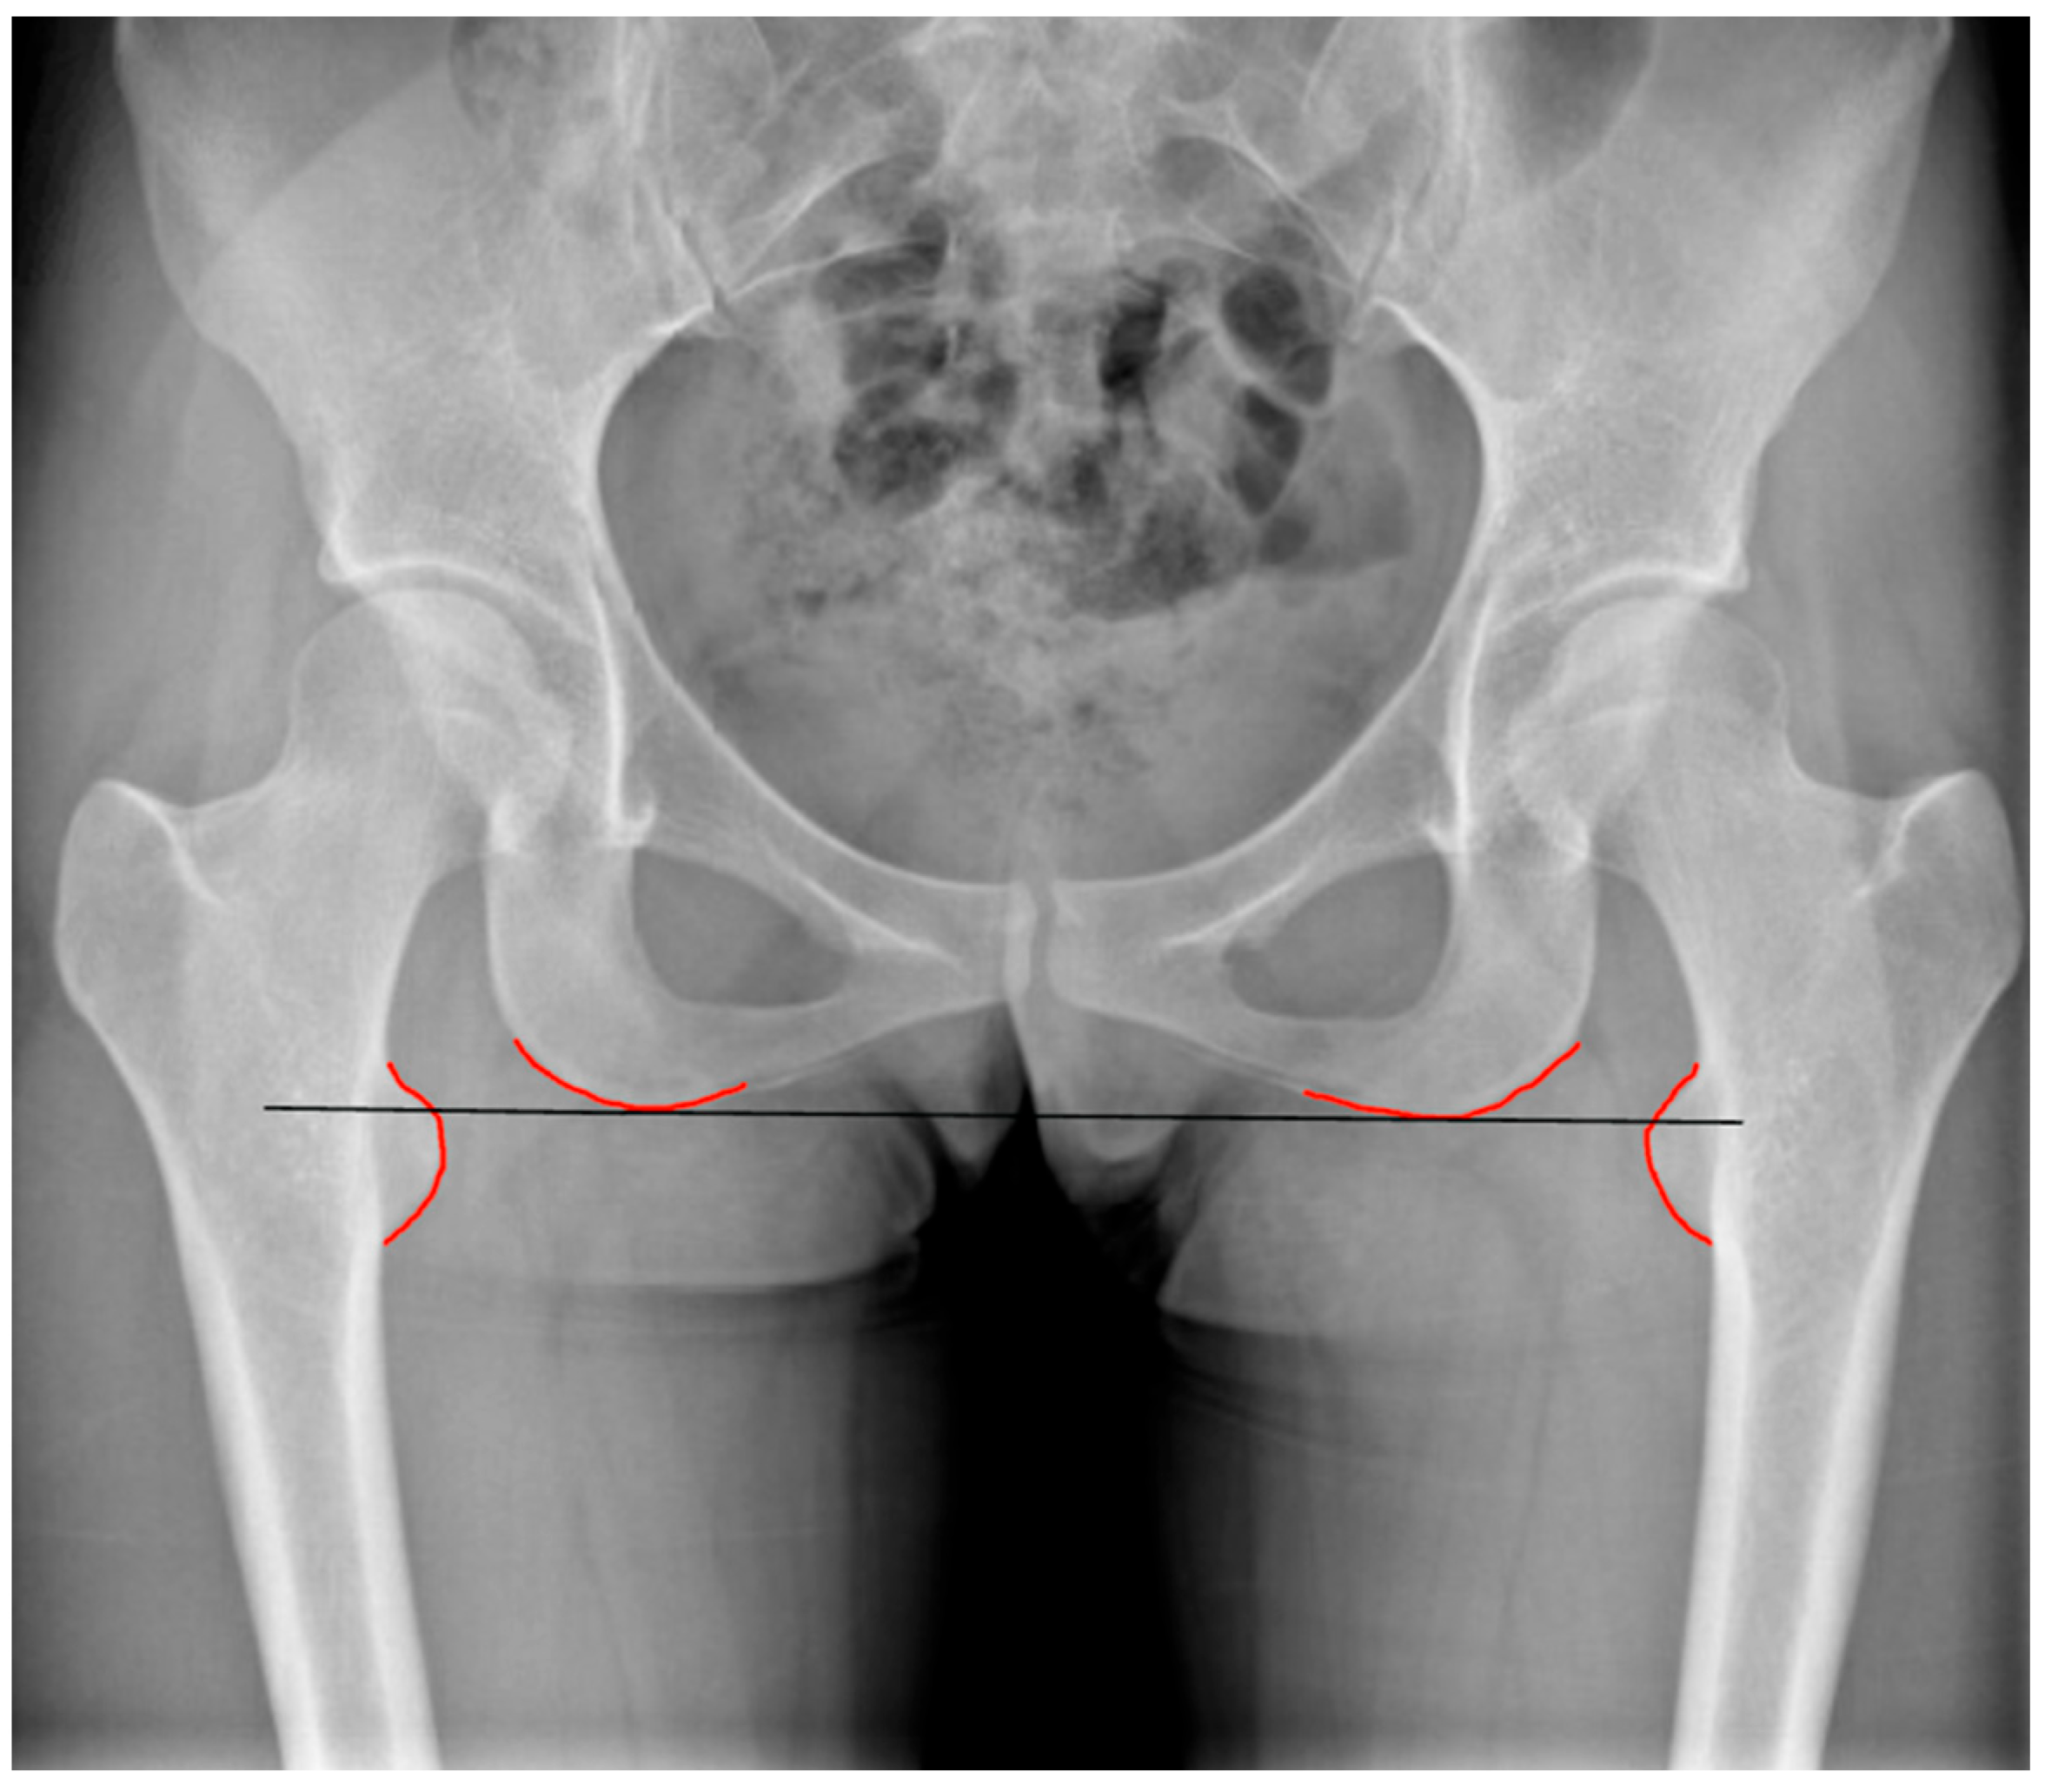

2. Anatomical and Functional Lower Limb Discrepancy: Definition and Assessment

3. Lower Limb Discrepancy in THA

4. Preoperative Planning and Intraoperative Assessment